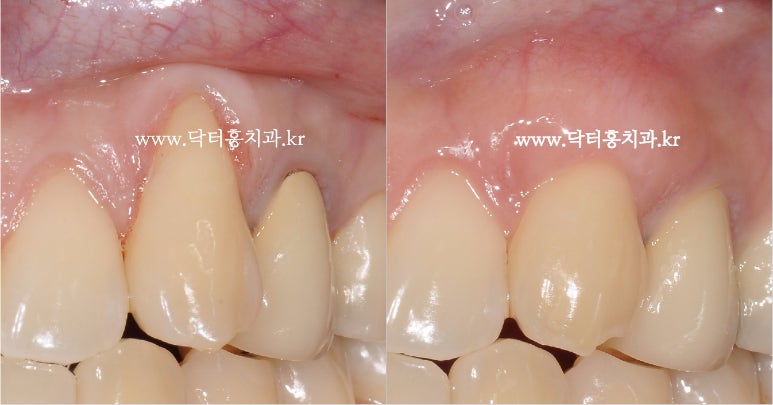

위의 경우도 교정치료 후 아랫앞니 잇몸이 없어지고 뿌리가 노출돼 잇몸재생술을 받아 오른쪽과 같이 개선됐다.잇몸 염증까지 생기고 거의 뿌리까지 잇몸이 없어진 경우이기 때문에 다소 늦게 오신 경우.오른쪽은 치료 후 모습으로 실제 이렇게까지 잘 될 것이라고 필자도 기대하지 않았다.이런 경우 치과의사로서 더 큰 보람을 느낄 수 있었던 경우.

위의 경우도 교정치료 후 아랫앞니 잇몸이 없어지고 뿌리가 노출돼 잇몸재생술을 받아 오른쪽과 같이 개선됐다.잇몸 염증까지 생기고 거의 뿌리까지 잇몸이 없어진 경우이기 때문에 다소 늦게 오신 경우.오른쪽은 치료 후 모습으로 실제 이렇게까지 잘 될 것이라고 필자도 기대하지 않았다.이런 경우 치과의사로서 더 큰 보람을 느낄 수 있었던 경우.